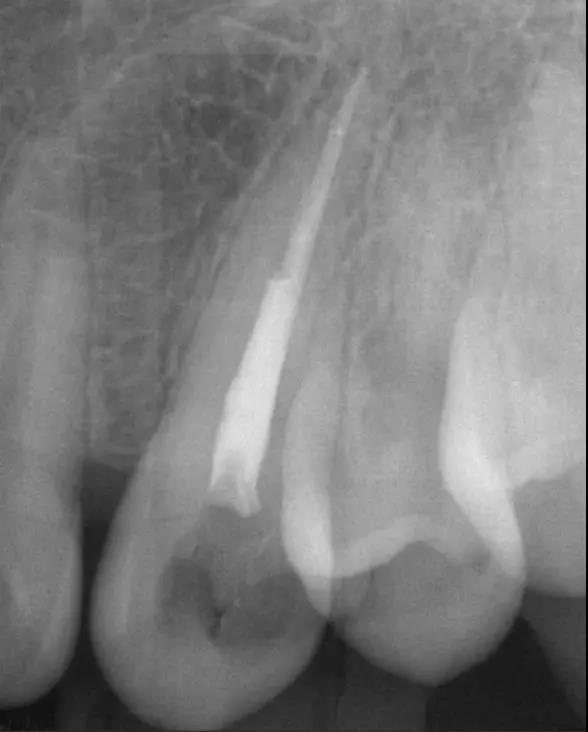

①小牙片:顾名思义,这种牙片很小,只能显示牙齿局部,但它能将局部放大,更加清晰地看到牙齿情况。根管治疗中,医生常需要小牙片辅助判断牙齿疼痛的原因。

②曲面断层或者CBCT:曲面断层多用于检查口腔整体状况,例如种植手术前查看牙槽骨骨量、下颌神经位置以及确定种植方案。